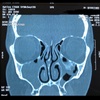

Sinusitis